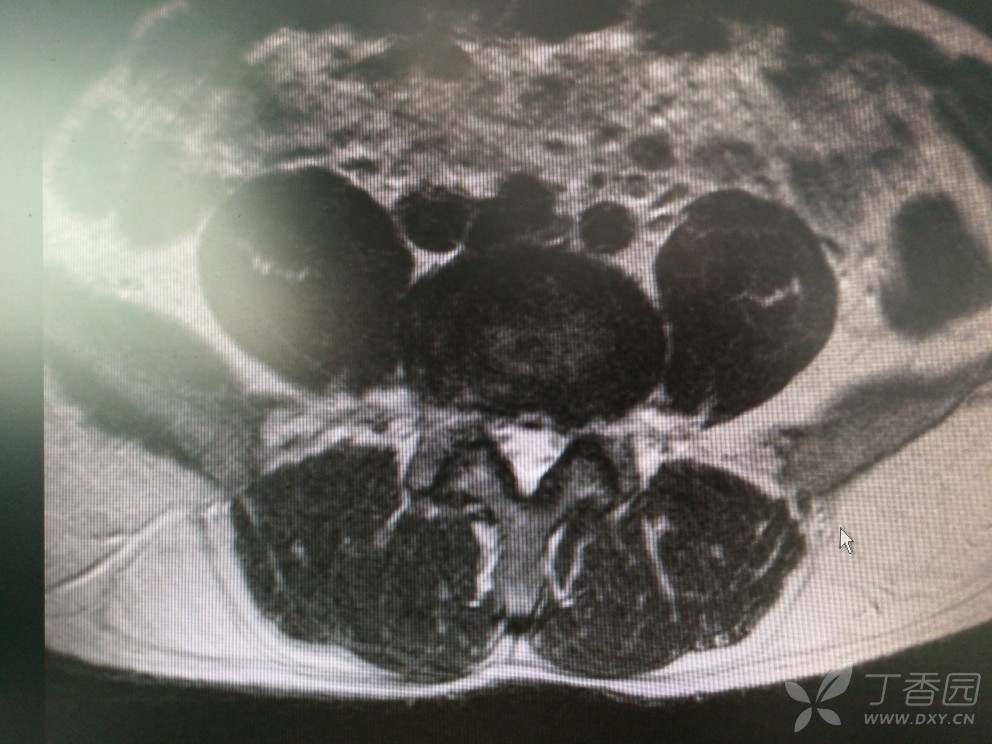

入院查MRI

我想问还是考虑L4/5 L5/S1椎间盘的变性引起的吗?